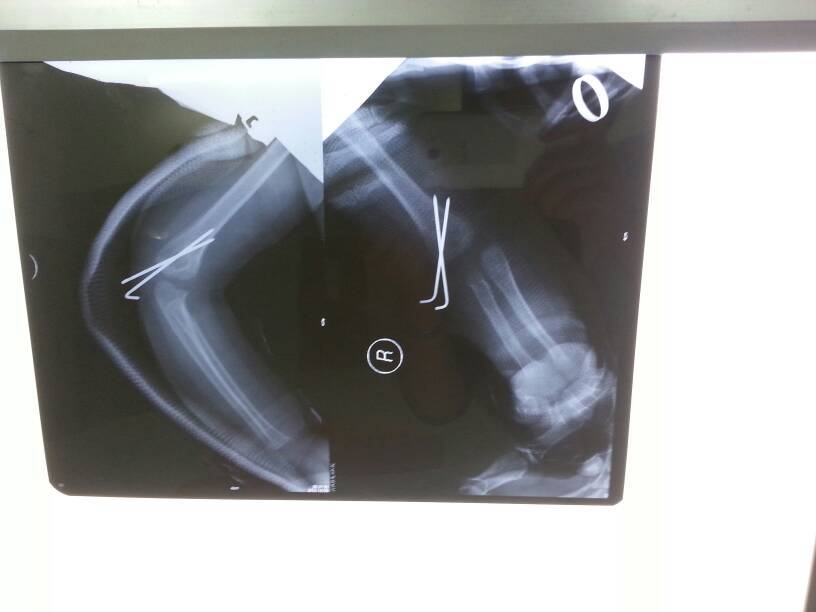

小孩一岁五个月,九月五号右肱骨骨骺分离行手法复位加克氏针固定,石膏克氏针固定四周,现在手屈能摸到耳朵,伸基本能直,但旋前充分,旋后差,伸直手臂感觉肘关节往上拱,肘部变大,上臂变细的感觉,现在每天在康复科做半小时左右功能锻炼,附术后四周的片子!从片子看对位是否达到解剖复位,以后会肘畸形吗?小孩塑形能力要多久?

病情分析: 您好,根据您提供的情况看,您的宝宝是右肱骨外上髁骨骺分离术后1个多月了。 指导意见: 从您提供的X光片看,宝宝的骨骺已经达到解剖复位。骨骺是生长骨质的部位,骨骺损伤后是非常容易导致骨骼生长过快或过慢,从而导致肢体发育畸形的,因此您的宝宝的情况是不能排除将来肘关节发育畸形的。小孩的塑形能力...是非常强的,一般塑形时间需要1-1.5年左右。